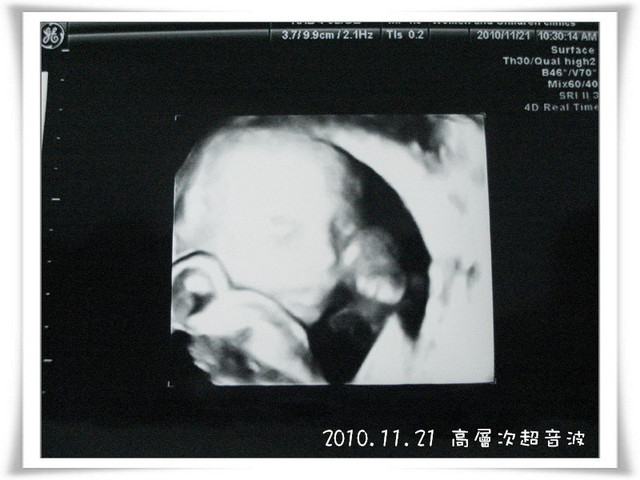

高層次超音波,又稱為詳細超音波或大型超音波,這跟一般產檢時所照的超音波其實是相同的

只是平常產檢時間有限,醫生無法很詳細的檢查寶寶各部位器官

基於對寶寶的關心,媽媽我還是花了大筆錢做這項自費檢查,順便讓自己安一下心